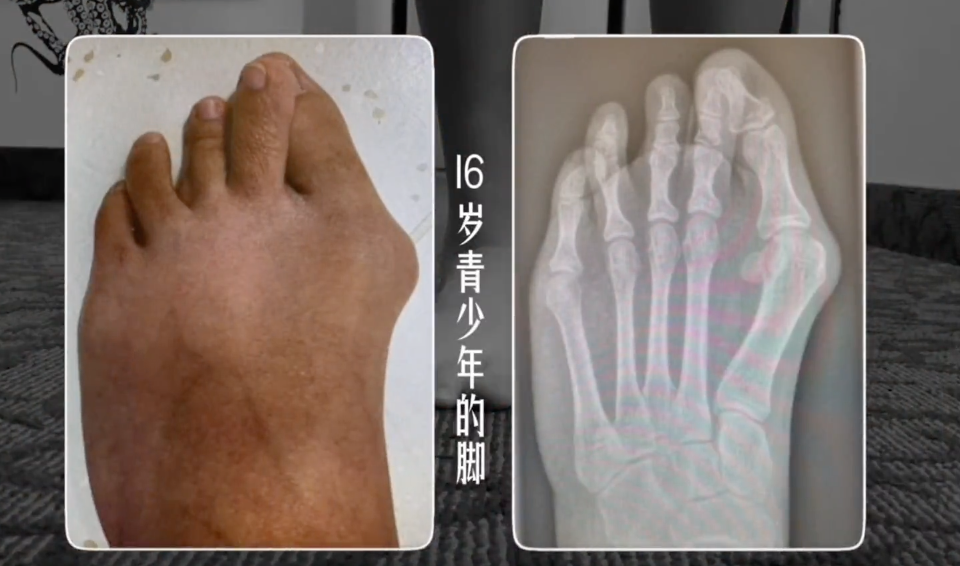

很多人以为大脚趾外翻只是“脚不好看”,但其实,它影响的不止是外形——腰痛、膝痛、髋关节不稳,甚至走路久了小腿酸、脚底痛,都可能和它有关。

当大脚趾开始“叛逃”向外,整个足弓结构就会跟着塌陷,久而久之,不仅走路姿势变形,连下肢的“力线”都乱了套。 教大家2个有效训练,帮你强化足底功能,重建下肢力线。